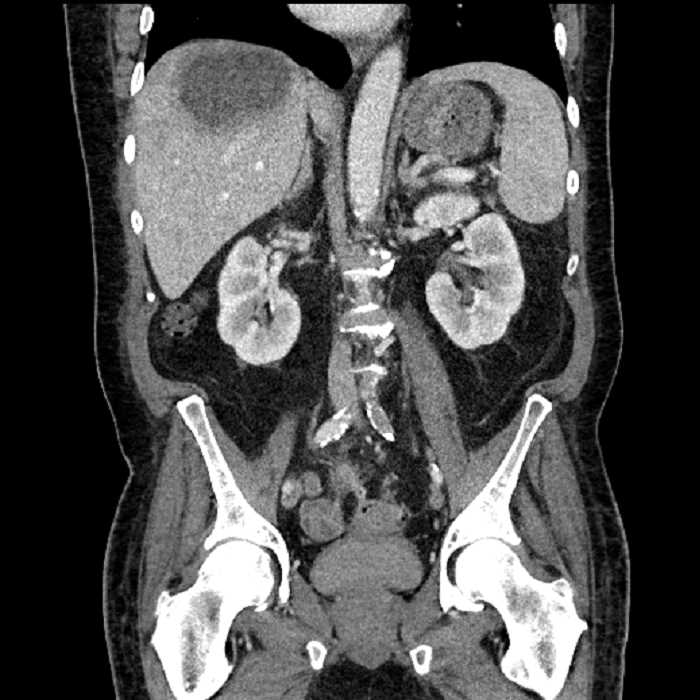

Age: 63

Sex: Male

Indication: Abdominal pain

• Large fluid density structure in hepatic segments 7 and 8 measuring 10 x 7 x 7 cm with internal septation and circumferential ill-defined low density compatible with edema

• Peripherally enhancing subcapsular collections along the anterior margin of the left hepatic lobe measuring 3 x 1 cm and 2 x 1 cm

• Clearly marginated fluid density structure in segment 7 and several other scattered tiny hypodensities, which likely represent cysts

• Hepatic abscess

Acute sigmoid diverticulitis complicated by a small contained perforation and a large abscess in the right hepatic lobe. Additional small subcapsular abscesses along the anterior margin of the left hepatic lobe.

• The classic CT imaging appearance is a double target sign with internal low density surrounded by an internal enhancing rim (capsule) and a low density external rim (edema)

Hepatic abscess showing the double target sign with low density internally surrounded by a thin inner enhancing rim (red arrow) and ill-defined outer low density rim (yellow arrow). Blue arrow indicates an internal septation. Red arrows: additional smaller subcapsular abscesses. Red arrow: focal contained perforation associated with diverticulitis.